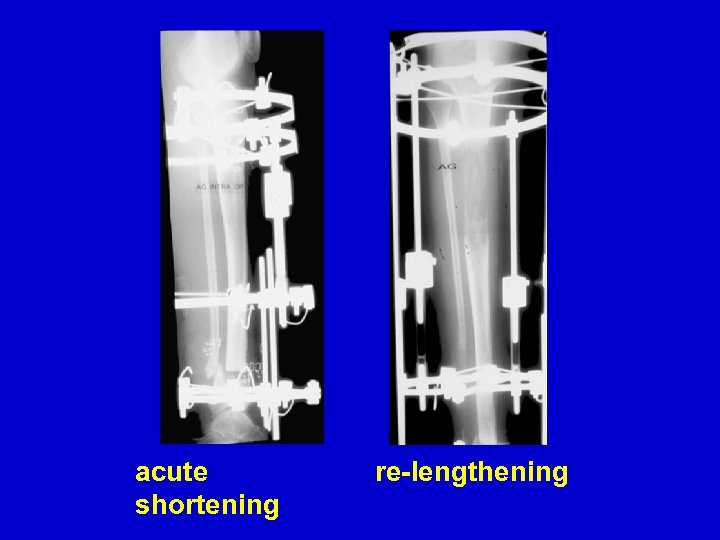

CPT resection

acute shortening re-lengthening

bone transport healed

Re. Fx IM rod follow-up